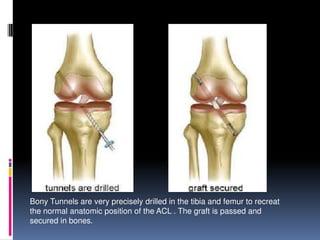

We’ll walk through an ACL reconstruction

Bony Tunnels are very precisely drilled in the tibia and femur to recreat

the normal anatomic position of the ACL . The graft is passed and

secured in bones.